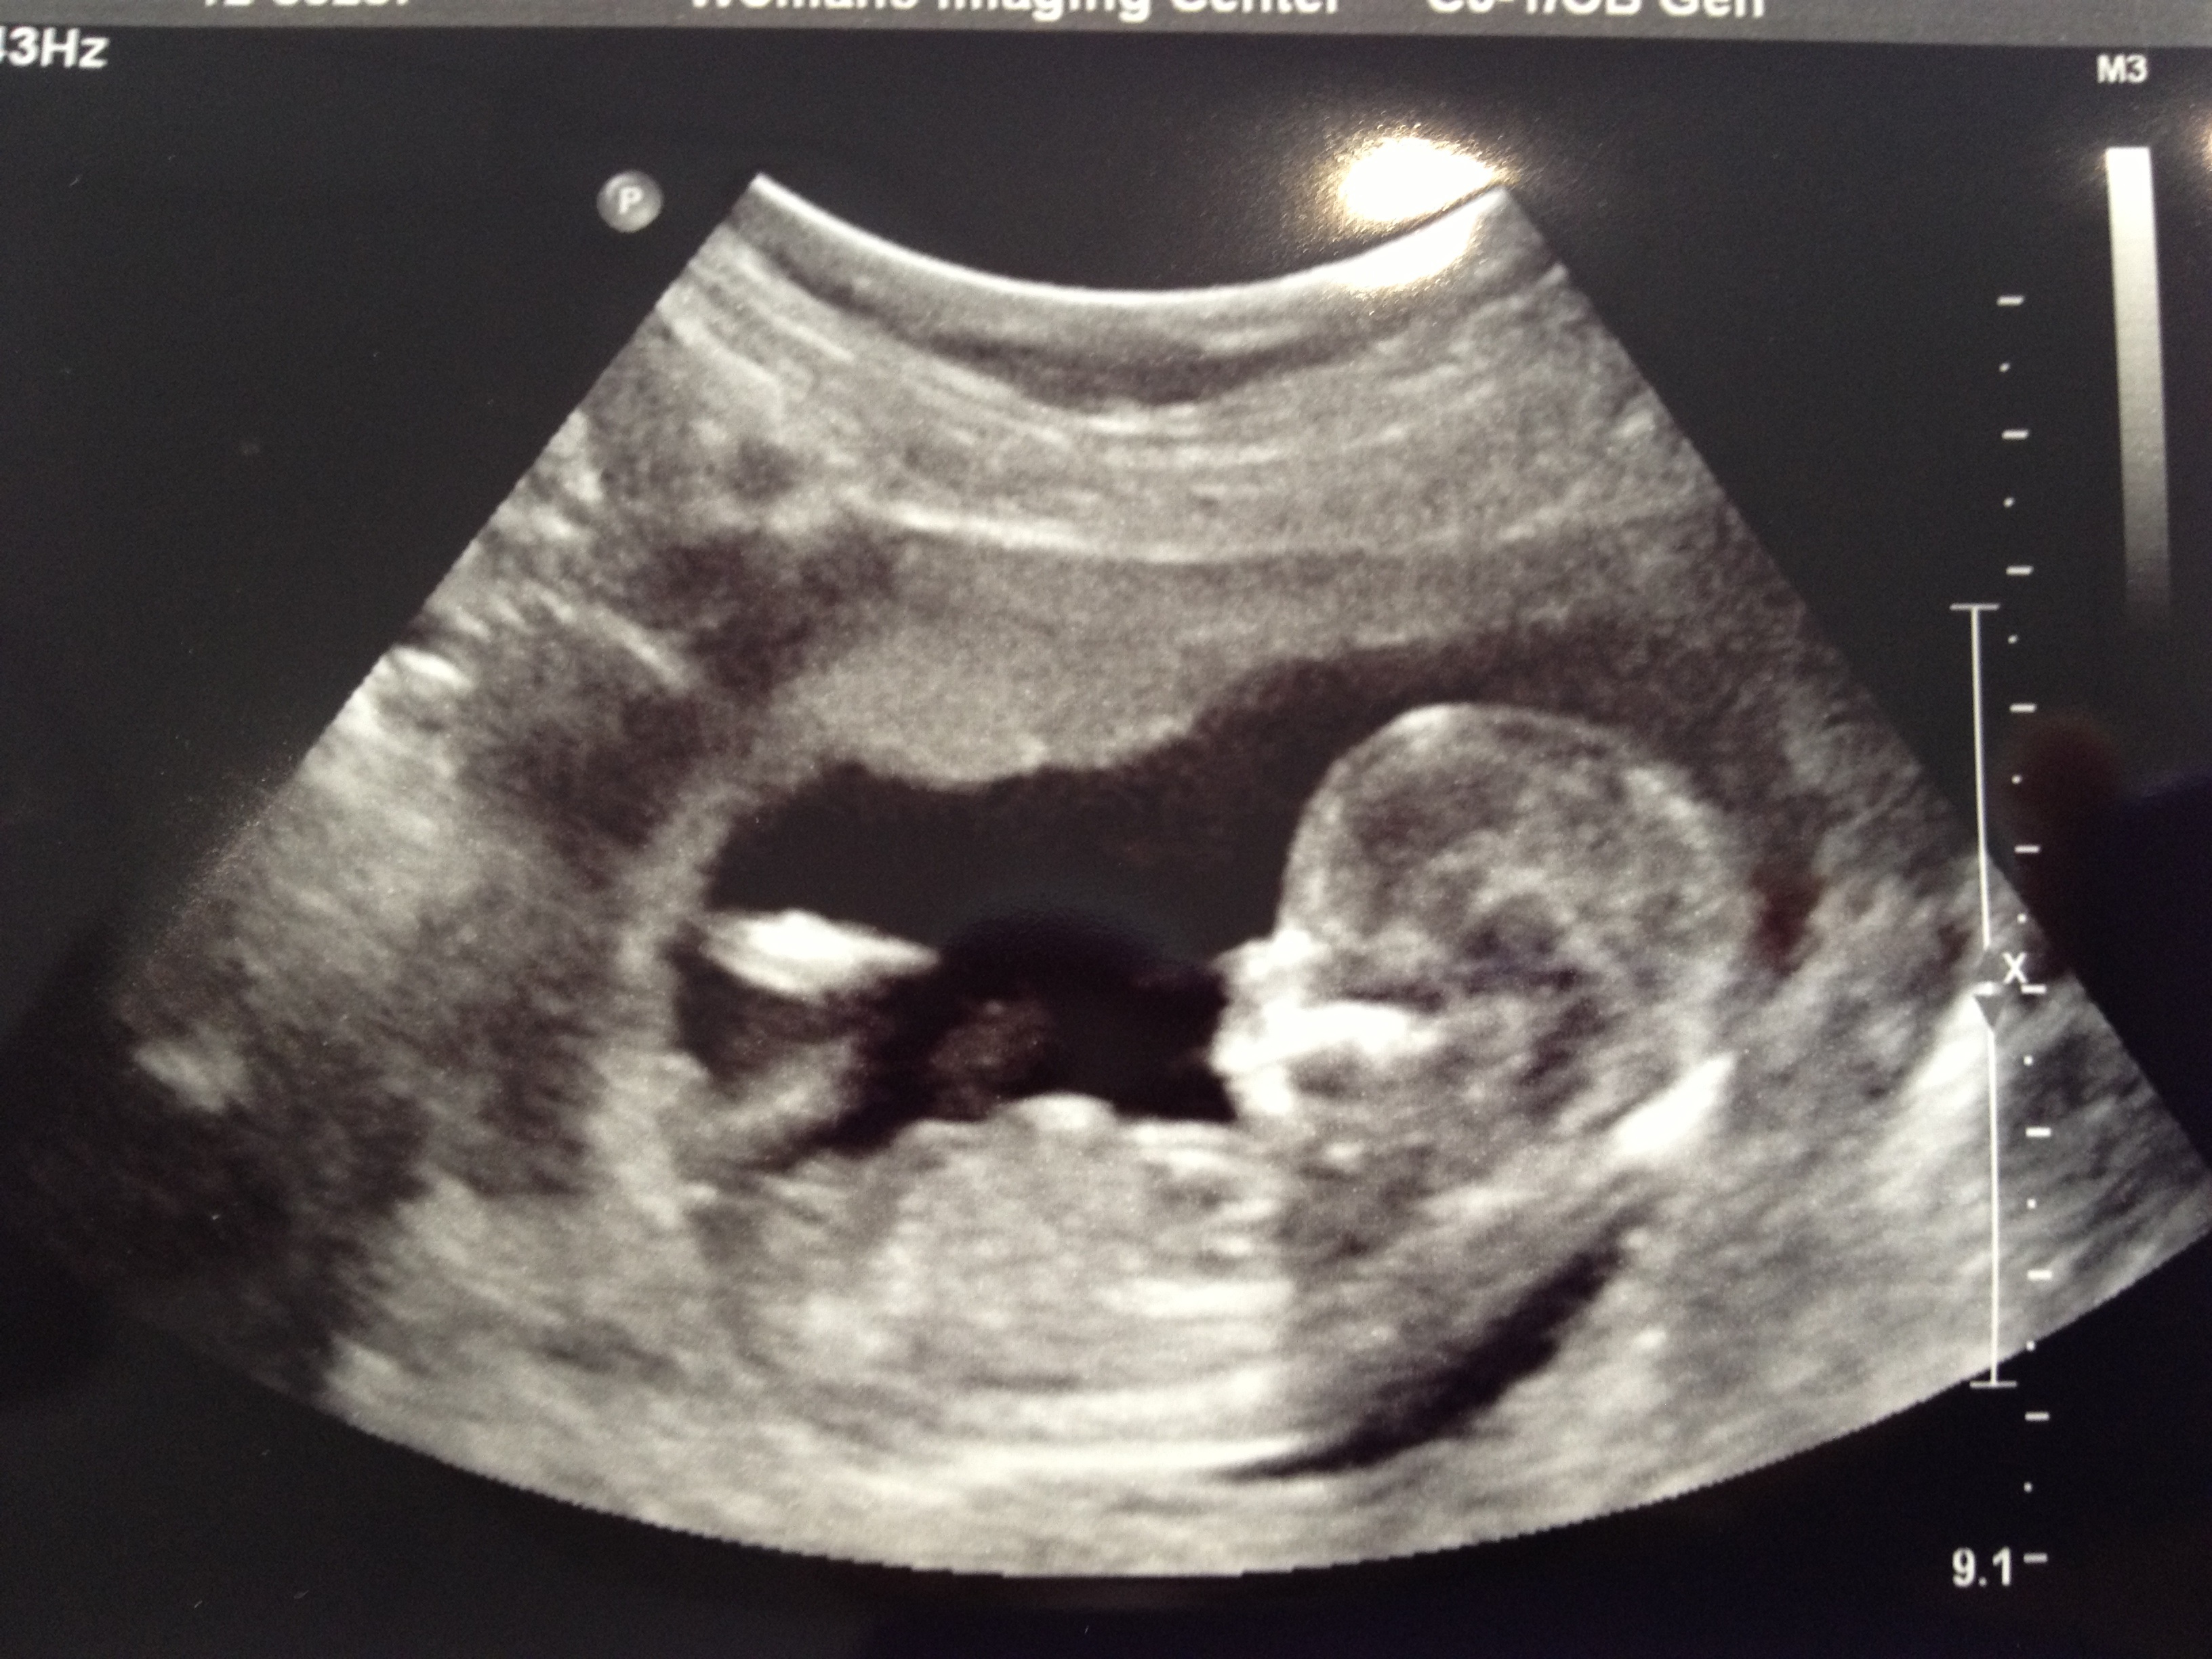

Of course the tech wouldn't say a word, but everything looked "normal" to me. And deuce was just in there wiggling around like crazy. I saw waving, kicking, and a full barrel roll. I love it! I see the OB tomorrow for the first time. Same one as with E though, and I really like her. Things are just trucking along.

UPDATE: I should have included a pic! Deuce wants to say hi to all of mommy's friends!